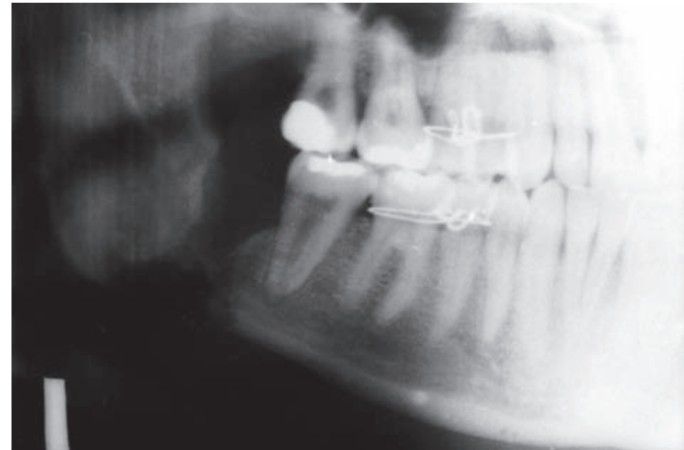

Chronic osteomyelitis

Chronic osteomyelitis in the region of mandiblular 3rd molar.